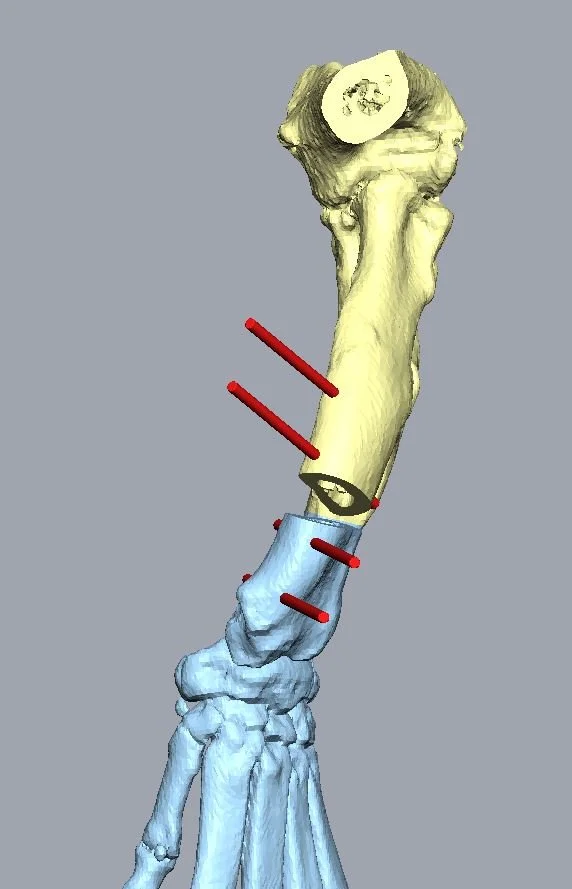

A thorough physical examination by a veterinarian is essential. In some cases, imaging techniques like X-rays or preferable CT scan may be employed to assess the severity and plan appropriate treatment.

Surgical Intervention:

There are various ways to deal with these conditions, the most successful cases are those treatted early on, and for which the deformity is assessed fully and corrected appropriately. The most recent techniques of 3D printing, bone modelling and design of customised surgical guides allow an increadible precision and planning for those procedures. Here at Gainsborough referrals, we can offer those state of art procedures from £5000.